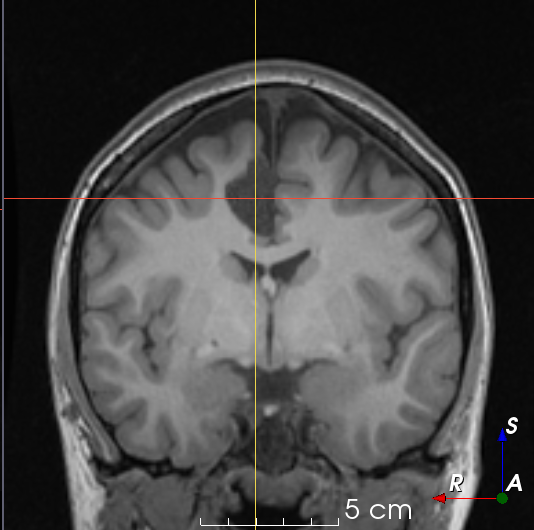

T1𝑇1T1-weighted MR images were collected from publicly available datasets Information eXtraction from Images (IXI) (566), Alzheimer’s Disease Neuroimaging Initiative (ADNI) (467), and Open Access Series of Imaging Studies (OASIS) (780), for a total of 1813 images. EPISURG was obtained from patients with refractory focal epilepsy who underwent resective surgery at the National Hospital for Neurology and Neurosurgery (NHNN), London, United Kingdom. This was an analysis of anonymized data that had been previously acquired as a part of clinical care, so individual patient consent was not required. In total there were 431 patients with postoperative T1subscript𝑇1T_{1}-weighted MR images, 269 of which had a corresponding preoperative MR image. All images were registered to a common template space using NiftyReg [17].